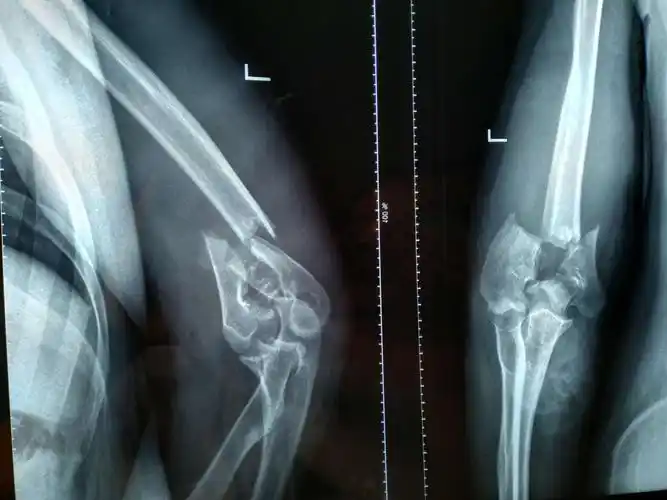

新年第一例肱骨髁上骨折

新年第一个肱骨髁上骨折骨折是否安排急诊

肱骨髁上骨折,求助 [病例帖]